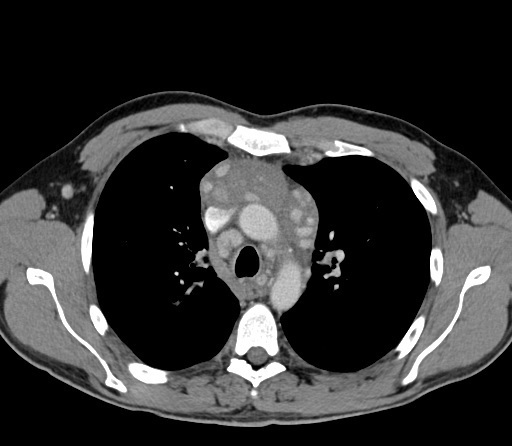

horseshoe lung associated with

scimitar syndrome